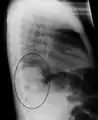

Right upper lobe pneumonia as marked by the circle.- Left upper lobe pneumonia with a small pleural effusion.